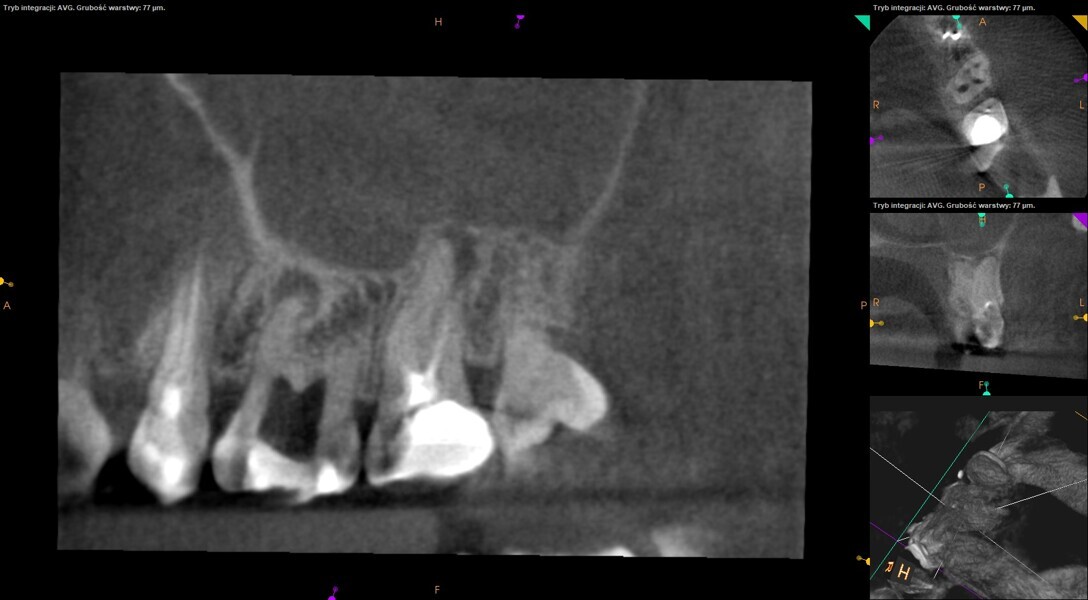

A 30-year-old female patient was referred to the office for non-surgical retreatment of the maxillary left first and second molars. The retreatment had been started by another dentist, but the case was referred after an unsuccessful attempt at locating the second mesiobuccal (MB2) canal. The CBCT imaging revealed two periapical lesions around the mesiobuccal roots of both molars. The retreatment was divided into two appointments.

At the first appointment, both teeth were opened, the old restorations were removed, all the root canal orifices were located and the first mesiobuccal (MB1), distobuccal (DB) and palatal canals were shaped. In both teeth, the MB2 orifices were located, but the canals were not shaped. The preparation phase was similar to that explained earlier. During the root canal preparation phase, the hand file was used to establish patency after each reciprocating instrument, and the canals were flushed with NaClO activated with the SkyPulse laser in SWEEPS mode for 10–15 seconds. After reaching two-thirds of the estimated working length with the reciprocating files, the LPE enhanced irrigation protocol with the SkyPulse laser was employed. The apical preparation was not performed at this stage. Owing to a lack of time at this appointment, the canals were flushed with EDTA and sterile water, and a 2% solution of chlorhexidine was poured as an intra-canal dressing. Both teeth were closed with temporary composite restorations.

At the second appointment, the temporary restorations were removed, and the chlorhexidine was washed out with sterile water and EDTA. After opening the orifice of the MB2 canal in the first molar, the operator was not able to reach patency in the canal. Therefore, the isthmus between the MB1 and MB2 orifices was opened with diamond-coated ultrasonic tips. Finally, patency was reached. Shaping the MB2 canal in the second molar was possible only to the place of the junction with the MB1 canal. The CBCT imaging had revealed previously that the MB2 canal should have its own lumen in the apical third, but the place of the junction was below the curvature. The possibility of locating this space without damaging the root was very poor. At this stage, the LPE enhanced irrigation protocol was performed again. After performing of the irrigation protocol, the apical preparation was performed for all the canals. The final irrigation protocol was performed with 5 minutes of constant flow of 5.25% NaClO for 2 minutes, alternating with 17% EDTA for 30 seconds, with 5.25% NaClO for 30 seconds and 17% EDTA for 30 seconds, and irrigation with 5.25% NaClO for 5 minutes. All the irrigants were activated with an EDDY sonic tip (VDW). After performing the periapical radiographs, a CBCT scan was performed to confirm the separate path of the sealer that filled previously unprepared spaces of the MB2 canals in both teeth. In both cases, it was clearly visible on the CBCT image that all the previously unprepared spaces were filled with the obturation material.